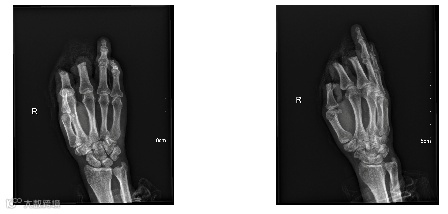

手外科医师对老周的右手做了清创操作,随后进行了右拇、食、中指离断局部转移皮瓣残端修整术。

伤成这样,老周的右手还能保留基本的手功能吗?

拇指食指对掌功能应该也还可以,所以像拿筷子,握手把等需要合掌的动作是可以的,但是精细的活动基本上就很困难了。